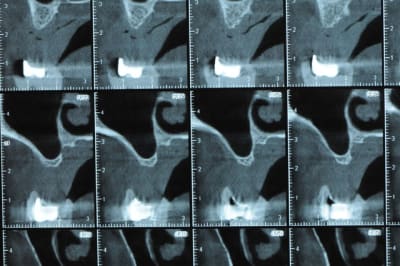

un cas pour PXAV.

ça c'est le domaine de pxav.

qu'en penses tu ?

j'ai besoin de 4 implants au maxillaire pour faire tenir son complet.

dans la zone postérieur, pas de problème, mais devant, c'est une autre histoire.

Non sans décorner, superbe cas de début pour expansion, bone splitting et tout et tout.

la corticale a l'air tiptop, par contre en cas d'expansion il faut eventuellemnt augmenter le nombre d'implant à 6 pour compenser eventuellement le manque d'epaisseur 'avis personnel)

Je suis sceptique sur la gestion de ce cas par bone splitting puisqu'il met parait très difficile d'obtenir un volume osseux peri-implantaire crestal suffisant et satisfaisant.

+1 Olive, ce serait à mon avis plus prédictible avec des greffes. Je doute qu'on puisse obtenir suffisamment d'os en vestibulaire et en palatin des implants en splittant une crête aussi fine.

De ce que j’ai vu du cas de D57 c’est me semble t il un magnifique cas d’expansion, ce qui ne veut pas dire rien d’autre

Ce n'est pas vraiment un consensus mais plutot du bon sens. Si tu as une crête en profil de lame de couteau cela signifie que tu as une fusion des corticales vestibulaire et palatine et donc absence de spongieux, ce qui comme tu le sais n'est pas indiqué en implanto (cj os de marbre par exemple)

Il me semble que Palti ou encore Szmukler-Moncler recommandent un minimum de 2-3mm. Si c'est plus fin, greffe d'apposition et GBR.

Dans ton cas il te faudrait abaisser la crête de 3 bons mm pour arriver à cette épaisseur.

Une petite étude de ton cas D57

Sous réserves bien sur de voir l’animal en vrai

Les zones exploitables radiologiquement parlant:

Coupes implant

2,3 40100

4,96 35130 avec sinus lift mais difficile

5,25 35150

6,02 35130

6,78 35115 après réduction de hauteur de crête

7,26 35115 après réduction de hauteur de crête

8,51 35150

10,43 40115 ou 50115

11,10 40115

Ce qui nous fait 9 implants possible évidement avec un comblement de sinus on augmenterait encore les zones implantable mais ce n’est pas le but recherché, avec 8 (4+4) il doit être possible de faire une belle barre support de complet